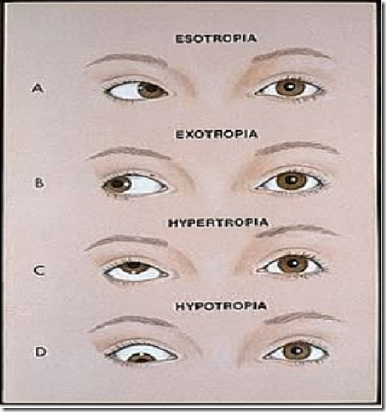

Ocular Movements & Visual Reflexes - Medatrio

medatrio.com

medatrio.com

movements ocular strabismus reflexes visual eye extraocular medial squint weakness medially right laterally muscles paralysis producing